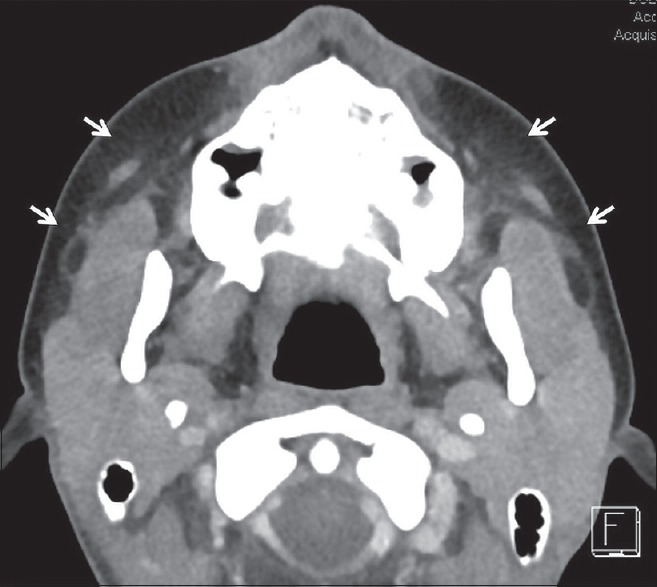

Pre-training data. We use the same dataset as LLaVA-Med (llava-med). Stage 1 includes 600K image-text pairs filtered from PMC-15M, converted into instruction-following data with simple image descriptions. Stage 2 comprises 60K image-text pairs from PMC-15M across five modalities: CXR, CT, MRI, histopathology, and gross pathology. GPT-4 is then employed to generate multi-round Q&A in a tone mimicking visual interpretation, converting these pairs into an instruction-following format.